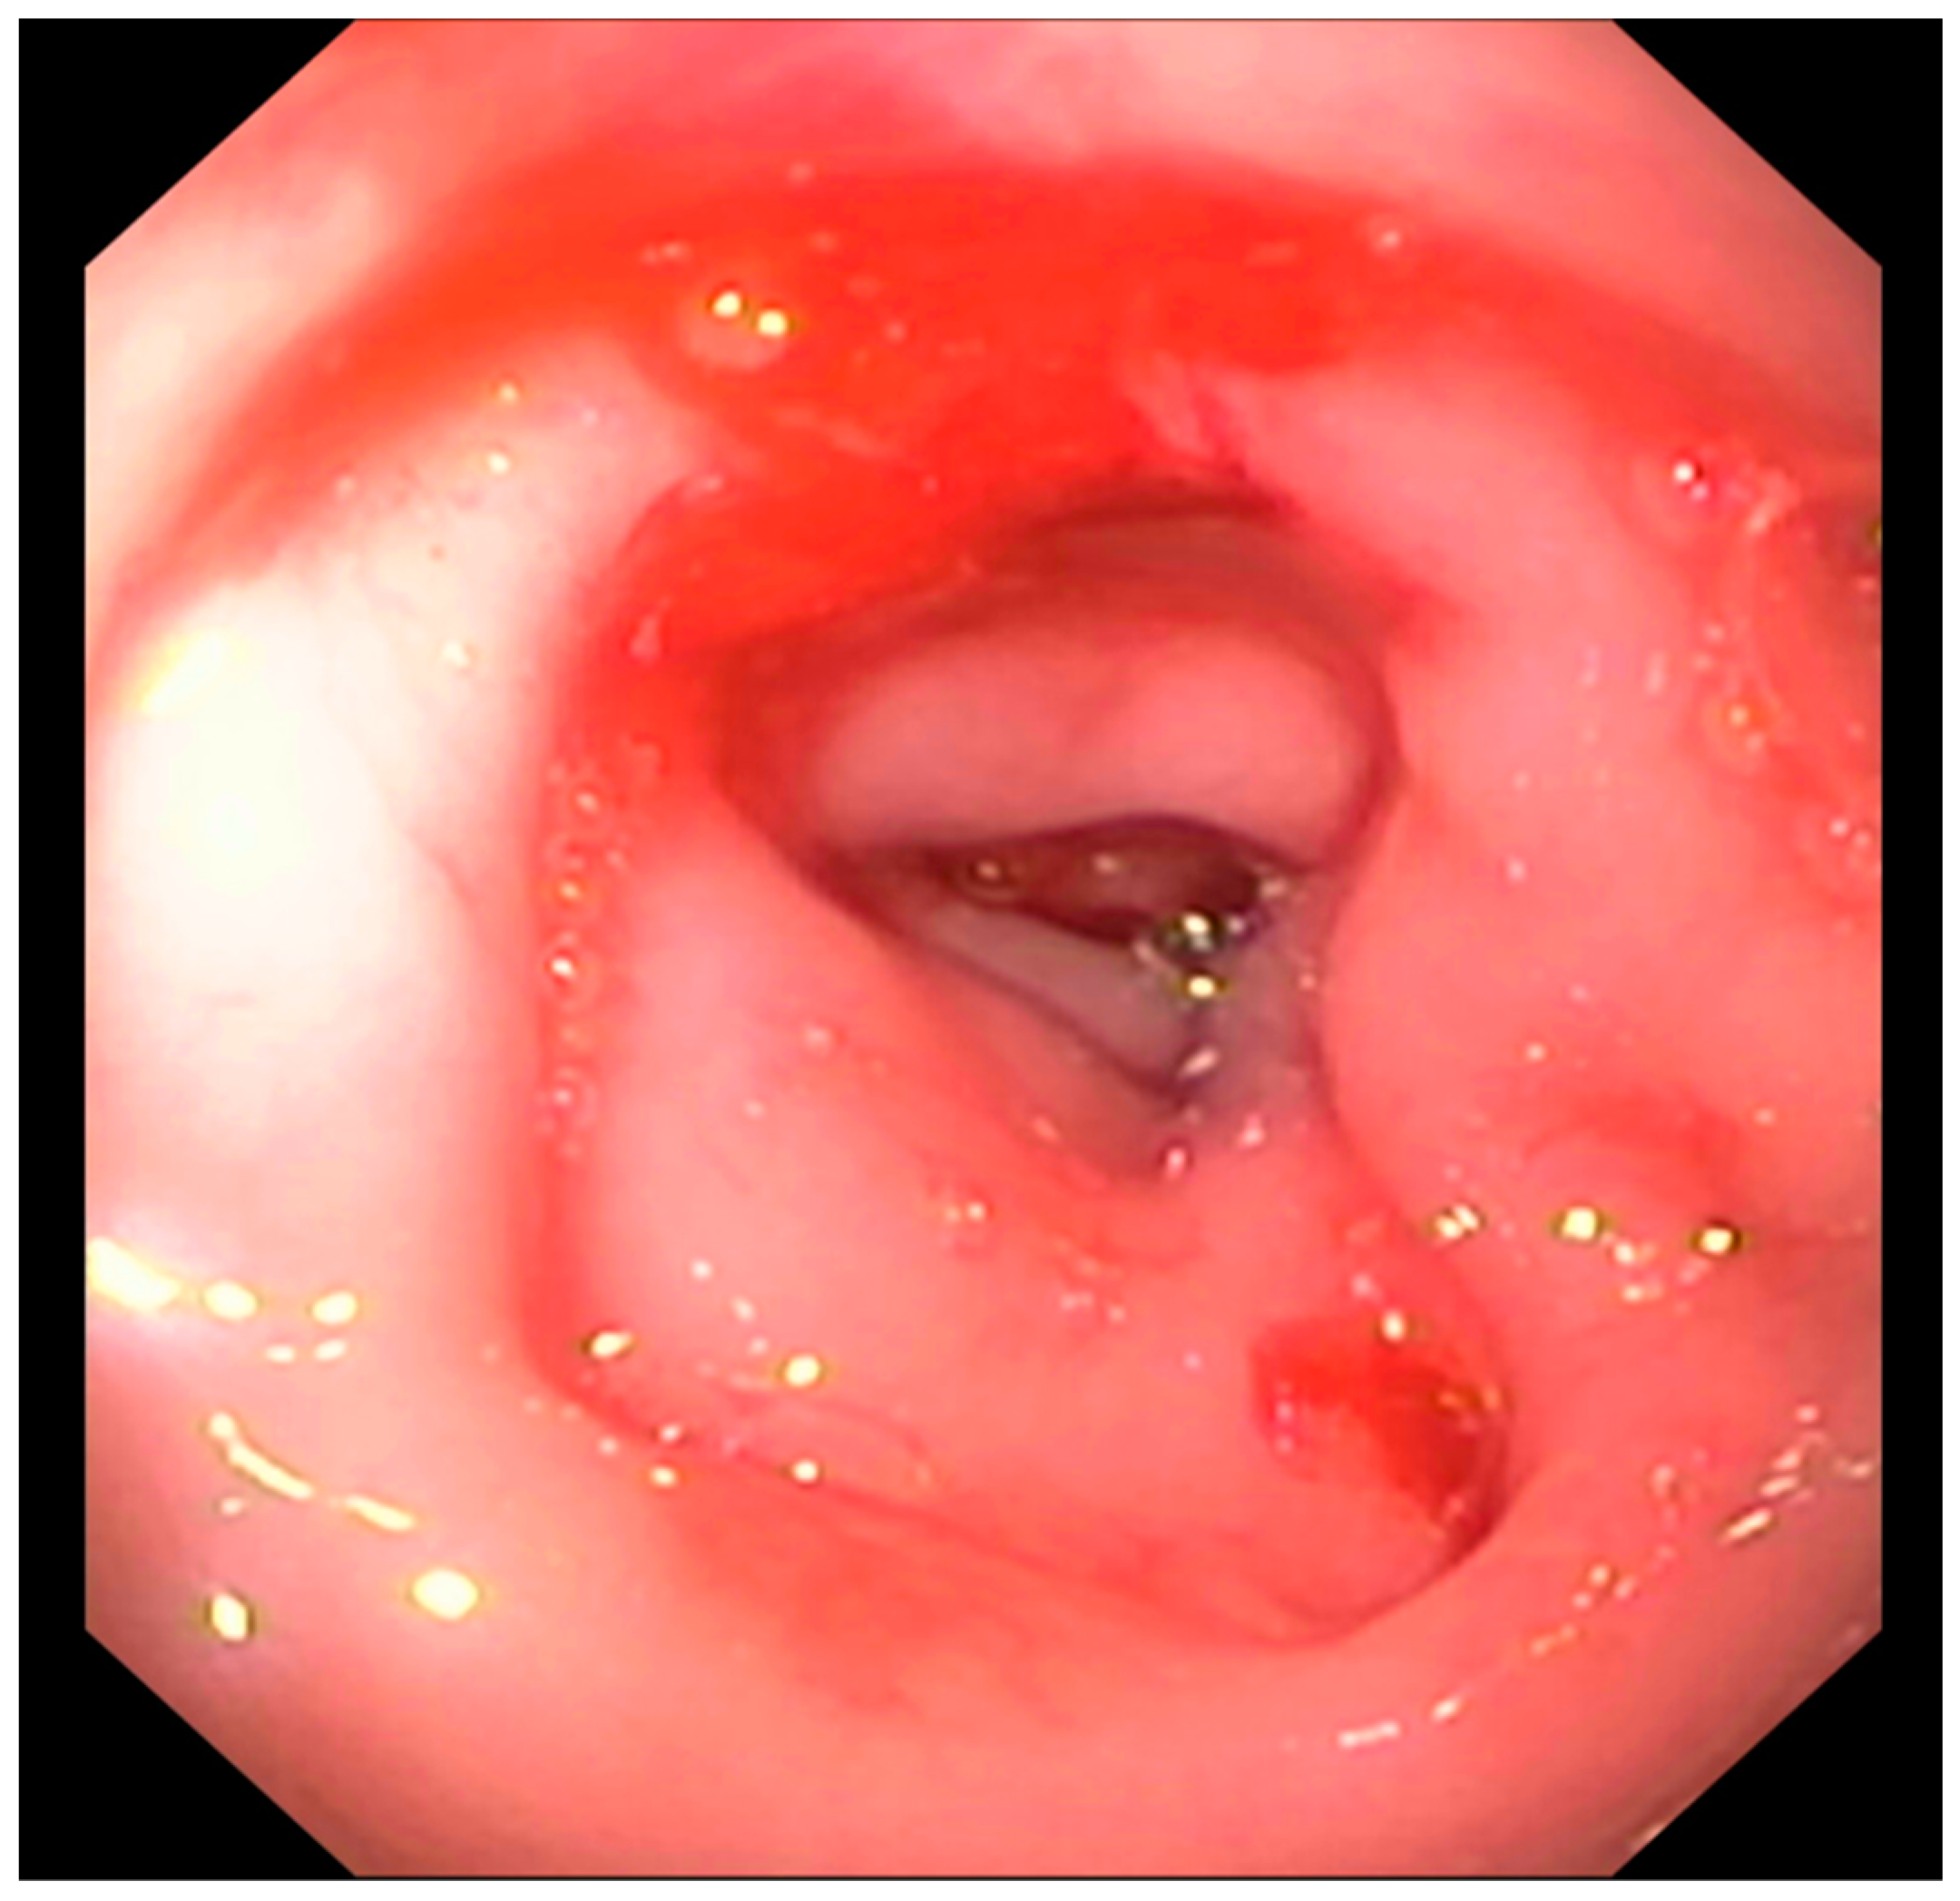

3.2.3. Abdominal Radiographs